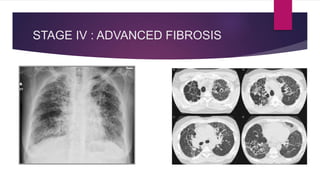

 By convention thoracic sarcoidosis is classified in four (04) stages on the basis

 Stage IV: Represents the development of irreversible pulmonary fibrosis

STAGE IV : ADVANCED FIBROSIS